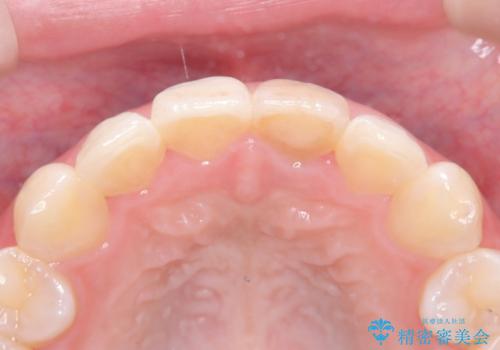

オールセラミッククラウンによる修復: 最終的な被せ物には、一切の金属を使用しないオールセラミックを選択。隣の天然歯と色調や透明感を精密に合わせることで、どこを治療したかわからないほど自然な仕上がりとなりました。